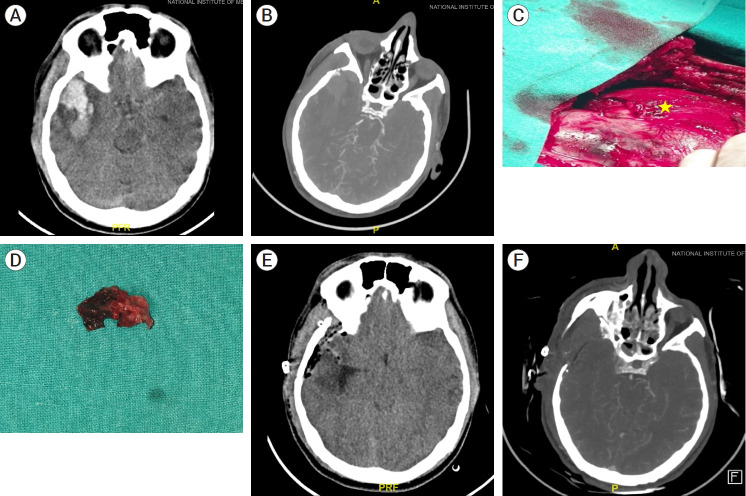

外伤性动脉瘤占颅内动脉瘤的比例不到 1%,脑膜中动脉假性动脉瘤更是罕见。外伤性动脉瘤通常是血管壁各层破裂形成的假性动脉瘤。由于可表现为硬膜外、硬膜下血肿,极少数可表现为实质内血肿,因此死亡率很高。然而,仅有 9 例外伤性脑膜中动脉假性动脉瘤表现为急性脑内血肿。我们报告了一例脑膜中动脉假性动脉瘤破裂并伴有脑实质内血肿的病例,并立即进行了血肿清除和动脉瘤切除术。患者术后恢复良好。此外,我们还查阅了文献中报道的所有脑膜中动脉假性动脉瘤病例,包括硬膜外血肿、硬膜下/实质内血肿或蛛网膜下腔出血。然而,术中确定动脉瘤的位置可能具有挑战性,因为血肿可能会掩盖动脉瘤的位置。与蝶骨脊的距离可作为术中的良好指导。如果能立即进行术中定位和手术清除,就能取得令人满意的效果。

Traumatic aneurysms represent less than 1 percent of intracranial aneurysms and middle meningeal artery pseudoaneurysms are even rare. Traumatic aneurysms are usually pseudoaneurysms formed by the rupture of all the layers of the vessel wall. They are associated with high mortality as they can present as epidural, subdural, and rarely intraparenchymal hematoma. However, only nine cases of traumatic pseudoaneurysms of middle meningeal artery are reported that have presented as an acute intracerebral hematoma. We report a case of ruptured pseudo aneurysm of middle meningeal artery presenting with intraparenchymal hematoma in which hematoma evacuation and aneurysm excision was done immediately. The patient recovered well in the post-operative period. In addition, we reviewed all cases of middle meningeal artery pseudoaneurysms reported in the literature either as extradural hematomas, subdural/intraparenchymal hematomas, or subarachnoid hemorrhages. However, identifying the location of the aneurysm intraoperatively may be challenging as the hematoma may obscure the same. Distance from the sphenoid ridge may serve as a good intraoperative guide. Intraoperative localization along with surgical evacuation if done immediately can lead to gratifying results.